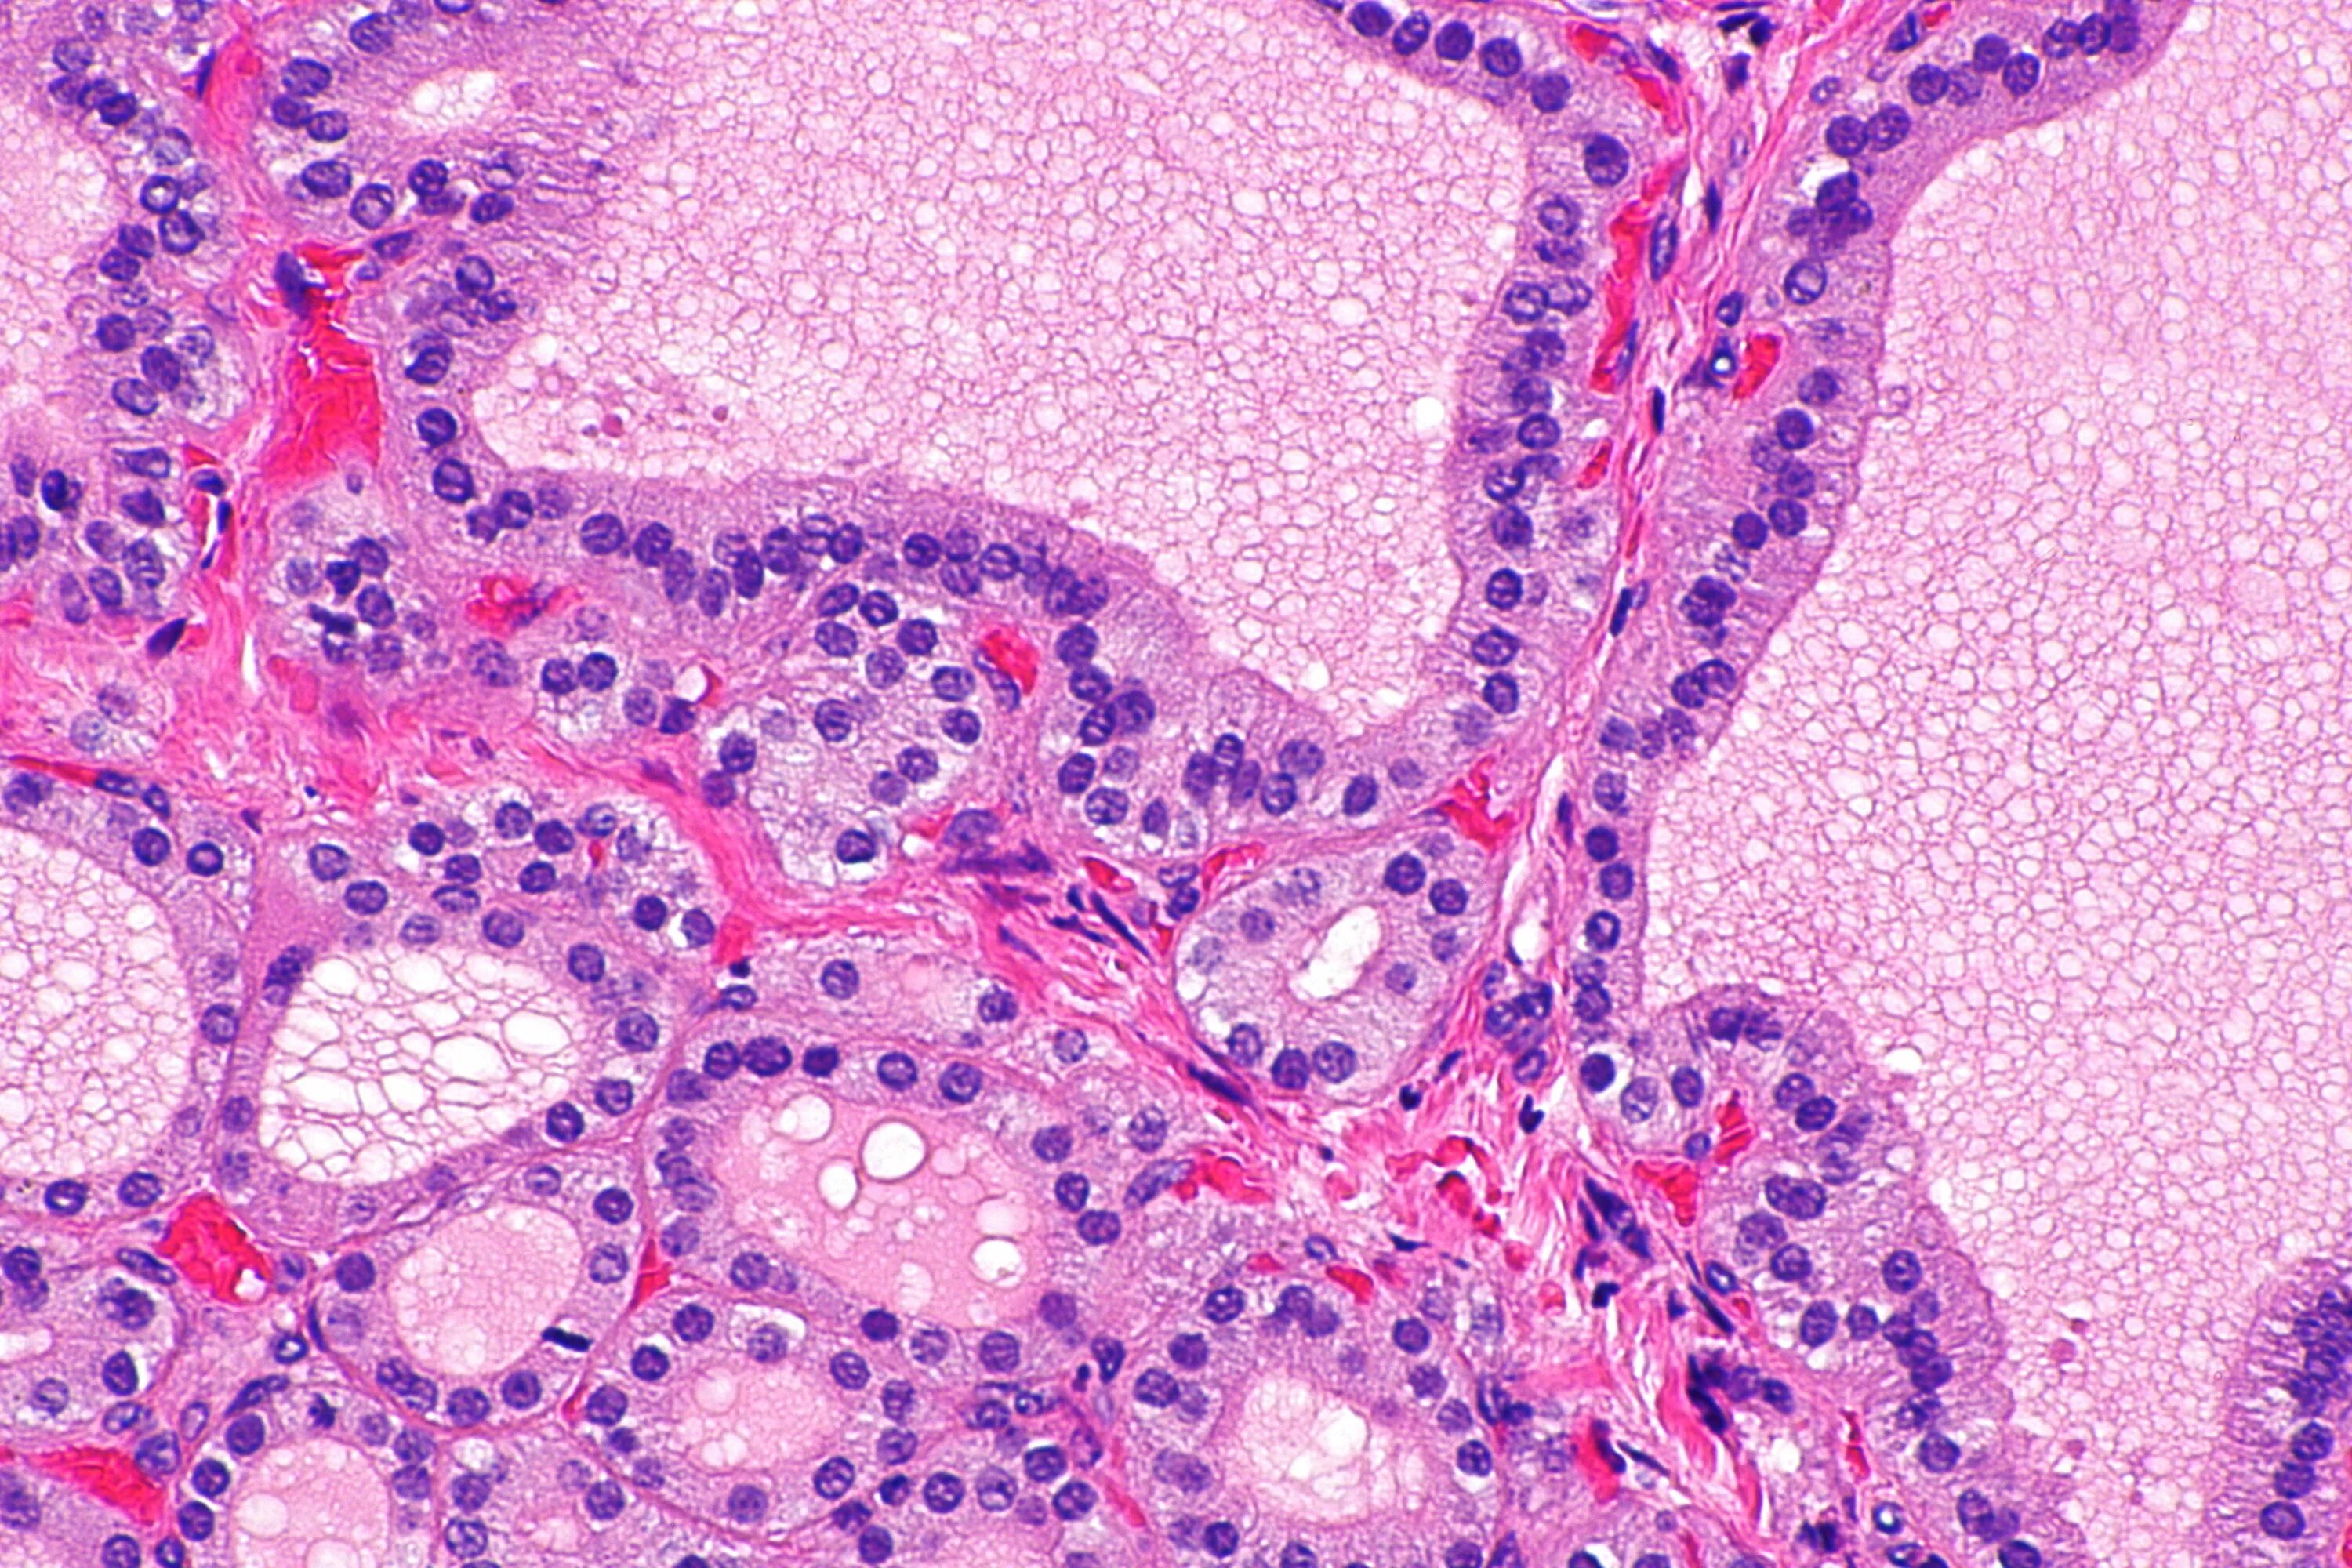

Гистологические заболевания